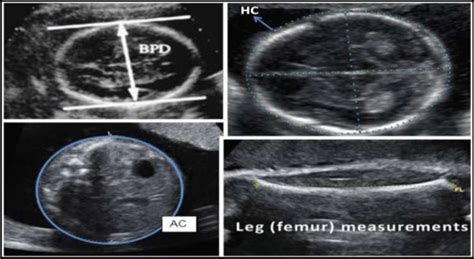

• BPD: Biparietal Diameter. This refers to the measurement of the baby’s head, specifically the distance across the head from one side to the other. Think of it as the width of your baby’s head. It’s a crucial measurement for estimating gestational age and tracking head growth throughout pregnancy. The sonographer will measure the widest part of the head, and this measurement is then compared to a chart to see if it falls within the expected range for the baby’s gestational age. Normal ranges vary slightly, but at 18 weeks, you’re usually looking at a BPD that’s somewhere in the ballpark of 4.0 to 4.6 centimeters. It’s important to remember that these are just averages, and every baby grows at their own pace. If your baby’s BPD is a little above or below these numbers, your doctor will consider other factors and, likely, won’t be alarmed as long as the other measurements are healthy and the growth pattern is consistent. BPD measurements also contribute to the estimated fetal weight, which is another important indicator of your baby’s well-being.

• HC: Head Circumference. This is exactly what it sounds like – the measurement around your baby’s head. It’s essentially a circumference measurement, providing information about the overall size of the head. HC is another important metric for assessing fetal growth and can be more accurate than BPD in some cases. It’s often used in conjunction with BPD to paint a more complete picture. The HC is measured by tracing the outer perimeter of the fetal skull. Similar to BPD, the HC measurement is compared to established norms for gestational age. At 18 weeks, a normal HC range typically falls between 13.5 to 16.5 centimeters. Variations within this range are common and generally not cause for concern. HC helps doctors monitor potential issues like microcephaly (smaller than normal head size) or macrocephaly (larger than normal head size), although these are usually assessed in conjunction with other clinical findings. Regular monitoring of the HC throughout the pregnancy helps to identify any unexpected changes in the head’s growth.

• AC: Abdominal Circumference. Moving down to the torso, the AC measures the circumference of your baby’s abdomen. This is a key indicator of fetal weight and overall body size. The AC measurement is particularly useful in assessing the baby’s nutrition and growth. It’s taken at the level of the baby’s stomach, and the sonographer will try to get a circular measurement around the abdomen. The normal range for AC at 18 weeks generally falls somewhere between 10.5 to 13.5 centimeters. This measurement can be influenced by various factors, including the baby’s genetics, the mother’s health, and the amount of amniotic fluid. AC is often closely monitored, as it can indicate potential problems like fetal growth restriction or macrosomia (excessive fetal growth).

• FL: Femur Length. Finally, we have the femur length, which is the measurement of the longest bone in your baby’s body – the thigh bone. This is a great indicator of skeletal development and can also help estimate gestational age. The femur length is taken from the top of the femur (near the hip) to the bottom (near the knee). Normal FL ranges at 18 weeks usually fall between 2.3 to 3.0 centimeters. The FL measurement, like the others, contributes to the estimated fetal weight, which is an important overall indicator of the baby’s health. Assessing the FL allows for detection of any potential skeletal abnormalities or growth issues. It’s all part of making sure the baby’s bones are developing properly.